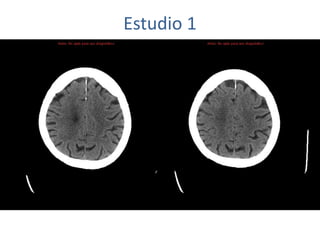

Estudio 1